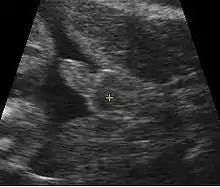

Obstetric sonogram of a fetus at 16 weeks. The bright white circle center-right is the head, which faces to the left. Features include the forehead at 10 o'clock, the left ear toward the center at 7 o'clock and the right hand covering the eyes at 9:00.